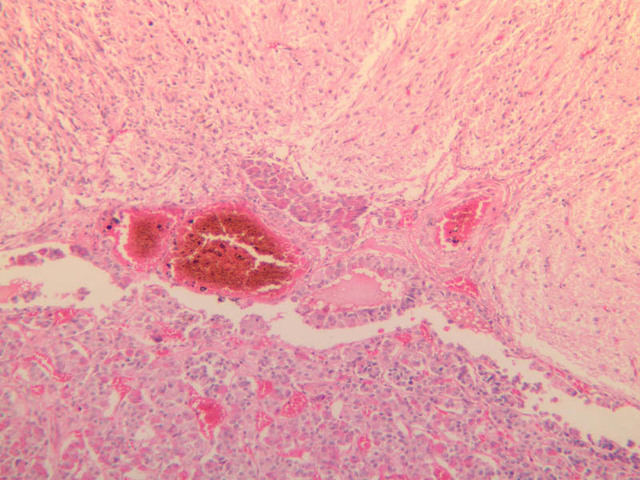

The adrenal gland (slide B-59, H&E [2.5x-labeled, 10x-labeled, 20x, 40x-labeled] [2.5x, 10x-labeled, 20x, 40x]; B-60, H&E [2.5x-labeled, 10x, 20x, 40x]; B-62, H&E [10x, 20x, 40x] [2.5x, 10x]) is a composite organ consisting of two functionally, structurally and embryologically different parts—an outer cortex and an inner medulla. Observe the gland at low power. Find the loosely organized tissue that comprises the medulla and the partially-separated columns of cells that make up the cortex. Scan the capsule and the tissue around it, looking for nerves and blood vessels. Study the pattern of cortical vasculature. In a pattern similar to that seen in the pars distalis of the pituitary, sinusoids run along the edges of columns or cords of cells. Owing to different arrangements of its constituent cells, the adrenal cortex has a layered appearance. From the capsule inward, these cortical layers are known as the zona glomerulosa, the zona fasciculata, and the zona reticularis.

The zona glomerulosa is located immediately beneath the capsule (B-60 adrenal gland, dog [10x, 20x] [20x, 40x]; B-59 [2.5x, 10x, 20x] [2.5x, 10x, 20x]). Its constituent cells are arranged in arcs or spheres, and, owing to their relatively small size, their nuclei appear to be close together. Cells of the zona glomerulosa secrete mineralocorticoids (e.g., aldosterone). The zona fasciculata consists of parallel columns or cords of cells that radiate toward the medulla and are separated by blood sinusoids (B-60 [2.5x, 10x, 20x, 40x]; B-62 [20x, 40x]). Owing to the extraction of lipids during histological processing, the cytoplasm of cells in the zona fasciculata appears highly vacuolated or "foamy". Cells of the zona fasciculata secrete glucocorticoids (e.g., hydrocortisone & cortisone) and some gonadocorticoids (weak androgens). The zona reticularis is the deepest cortical layer and lies adjacent to the medulla (B-60 [20x, 40x]; B-62 [20x, 40x]). It is characterized by irregular, interconnecting cords of cells which are separated by anastomosing capillary networks or sinusoids. Cells of the zona reticularis, which are smaller than those of zona fasciculata and do not contain as many lipid vacuoles, secrete gonadocorticoids and some glucocorticoids.

The medulla is composed of large epithelioid cells, arranged in small groups or cords which are separated by blood vessels. Usually, several large veins mark the center of the medulla. When fresh adrenal gland is incubated in solutions of chromium salts (as was the specimen on slide B-61), brownish precipitates form in the cells of the medulla-- hence, the name chromaffin cell (B-61, chromaffin [2.5x, 10x, 20x, 40x] [2.5x, 10x, 20x, 40x-labeled]). The more darkly stained chromaffin cells are known to contain norepinephrine, the less darkly stained cells, epinephrine. In essence, chromaffin cells are specialized postganglionic sympathetic neurons. How does the ultrastructure of these cells differ from that of the secretory cells of the adrenal cortex?